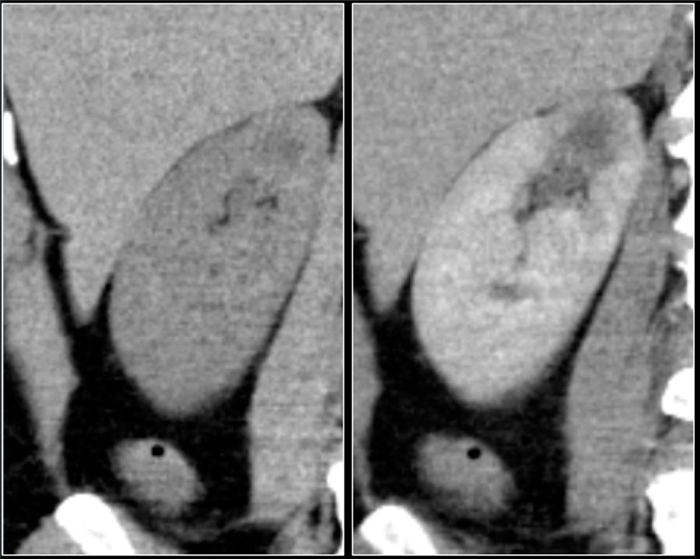

(Слева) МРТ, постконтрастное Т1-ВИ, аксиальная проекция: женщине 55 лет с фибрилляцией предсердий в анамнезе было проведено обследование на наличие образования почки; в правой почке была выявлена клиновидная зона с отсутствием контрастирования. Наличие кортикального ободка контрастирования и неизмененный контур почки указывают на то, что инфаркт острый или подострый.

(Справа) На соответствующем Т2-ВИ у этой же пациентки было выявлено снижение интенсивности Т2-сигнала в зоне инфаркта. (Слева) КТ в динамике, аксиальная проекция: у этой же пациентки спустя год выявлено прогрессирование инфаркта с атрофией и деформацией контура в поврежденной области.